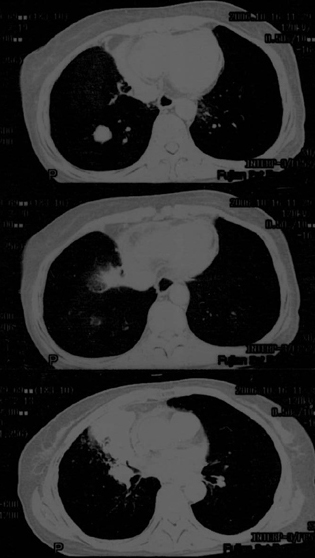

母亲67岁,咳嗽,无血痰。发病已两月余,抗生素无效

传上图片看不清,可是给我的感觉是恶性的,虽然还需跟肺结核相鉴别.

片子不清,右肺下叶像个结核球,右肺上叶需要做个支气管镜检查,除外中心型肺癌。个人意见,其他老师们再看看。